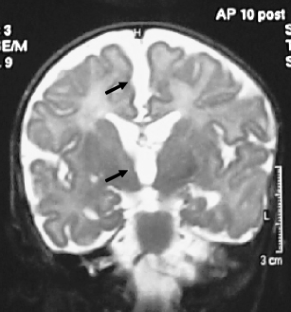

Fig. 2